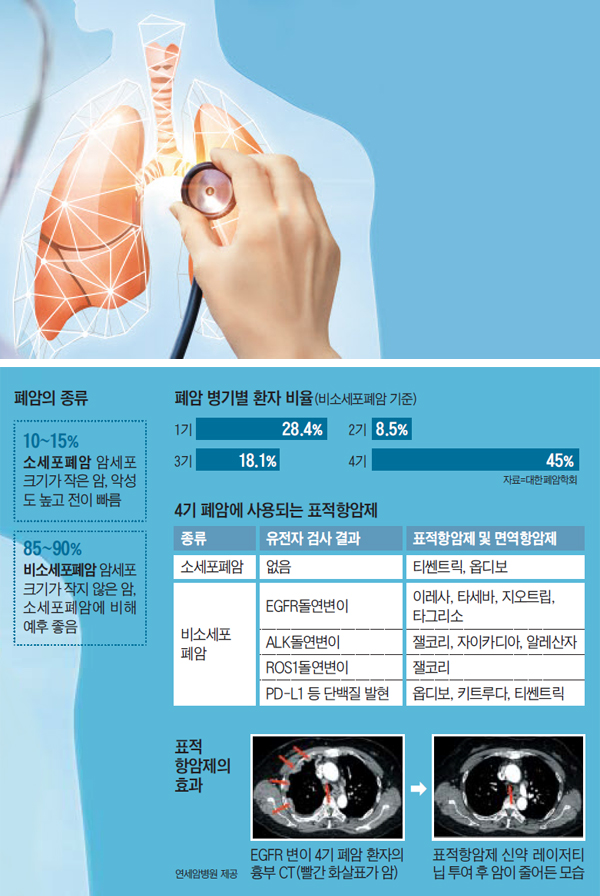

우리 엄마는 비소세포폐암의 일종인 선암종을 앓고 계십니다. (비소세포폐암과 소퍼폐암은 크기가 작은지 큰지에 따라 다음과 같이 정의됩니다)

비소세포폐암에서도 유전적 변이를 일으키는 표적항암제를 찾을 수 있다고 한다.

표적항암치료는 정상세포의 유전적 돌연변이로 인해 암세포가 형성되고, 이러한 돌연변이된 세포만을 집중적으로 치료하는 치료법이다.

첫 번째 단계는 유전적 돌연변이에 맞는 약물을 찾는 것이지만, 유전적으로 맞지 않더라도 면역치료나 표적치료제는 사용할 수 있다. (여기서부터는 경제적 측면과 관련이 있습니다.) 이런 표적치료나 치료를 받으면 이전보다 상당한 기간 동안 더 나은 반응을 유지할 수 있다고 합니다. 아무튼 기대됩니다~~!!!!